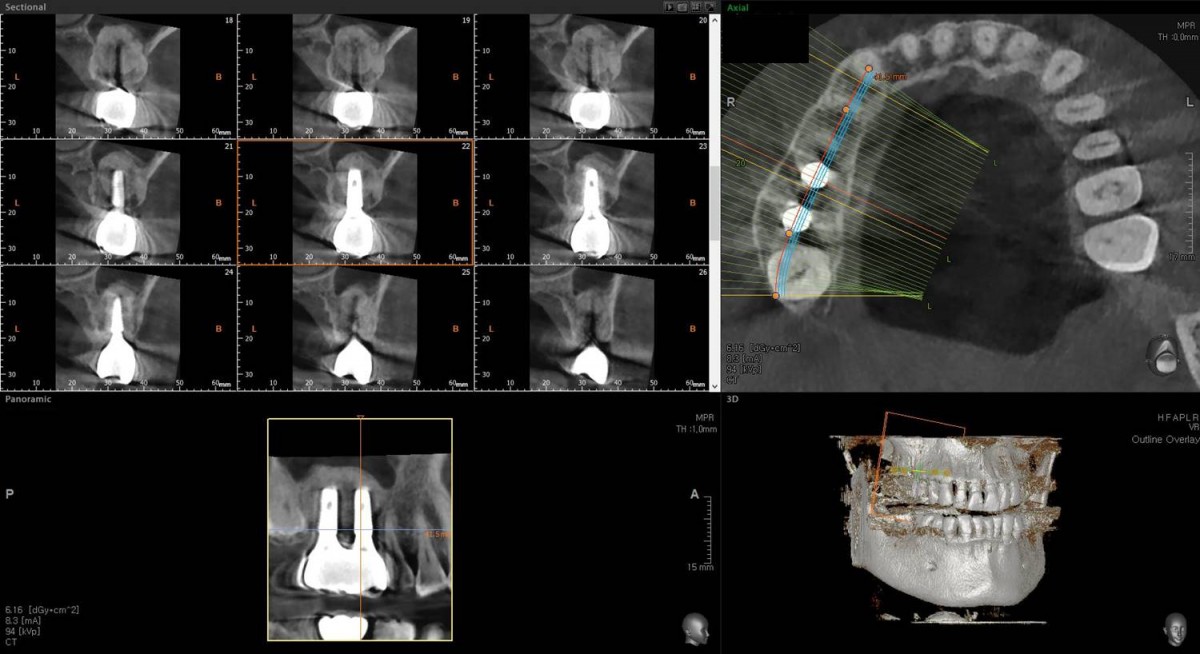

Maxillary Sinus Graft, 2 Implants, Crown Contouring

<GCaks> A 56-year-old male patient had pain-inducing caries, and perio-involved tooth mobility resulted in a tooth fracture at 1st molar. And it was removed months ago. He was a heavy smoker and showed poor oral hygiene.